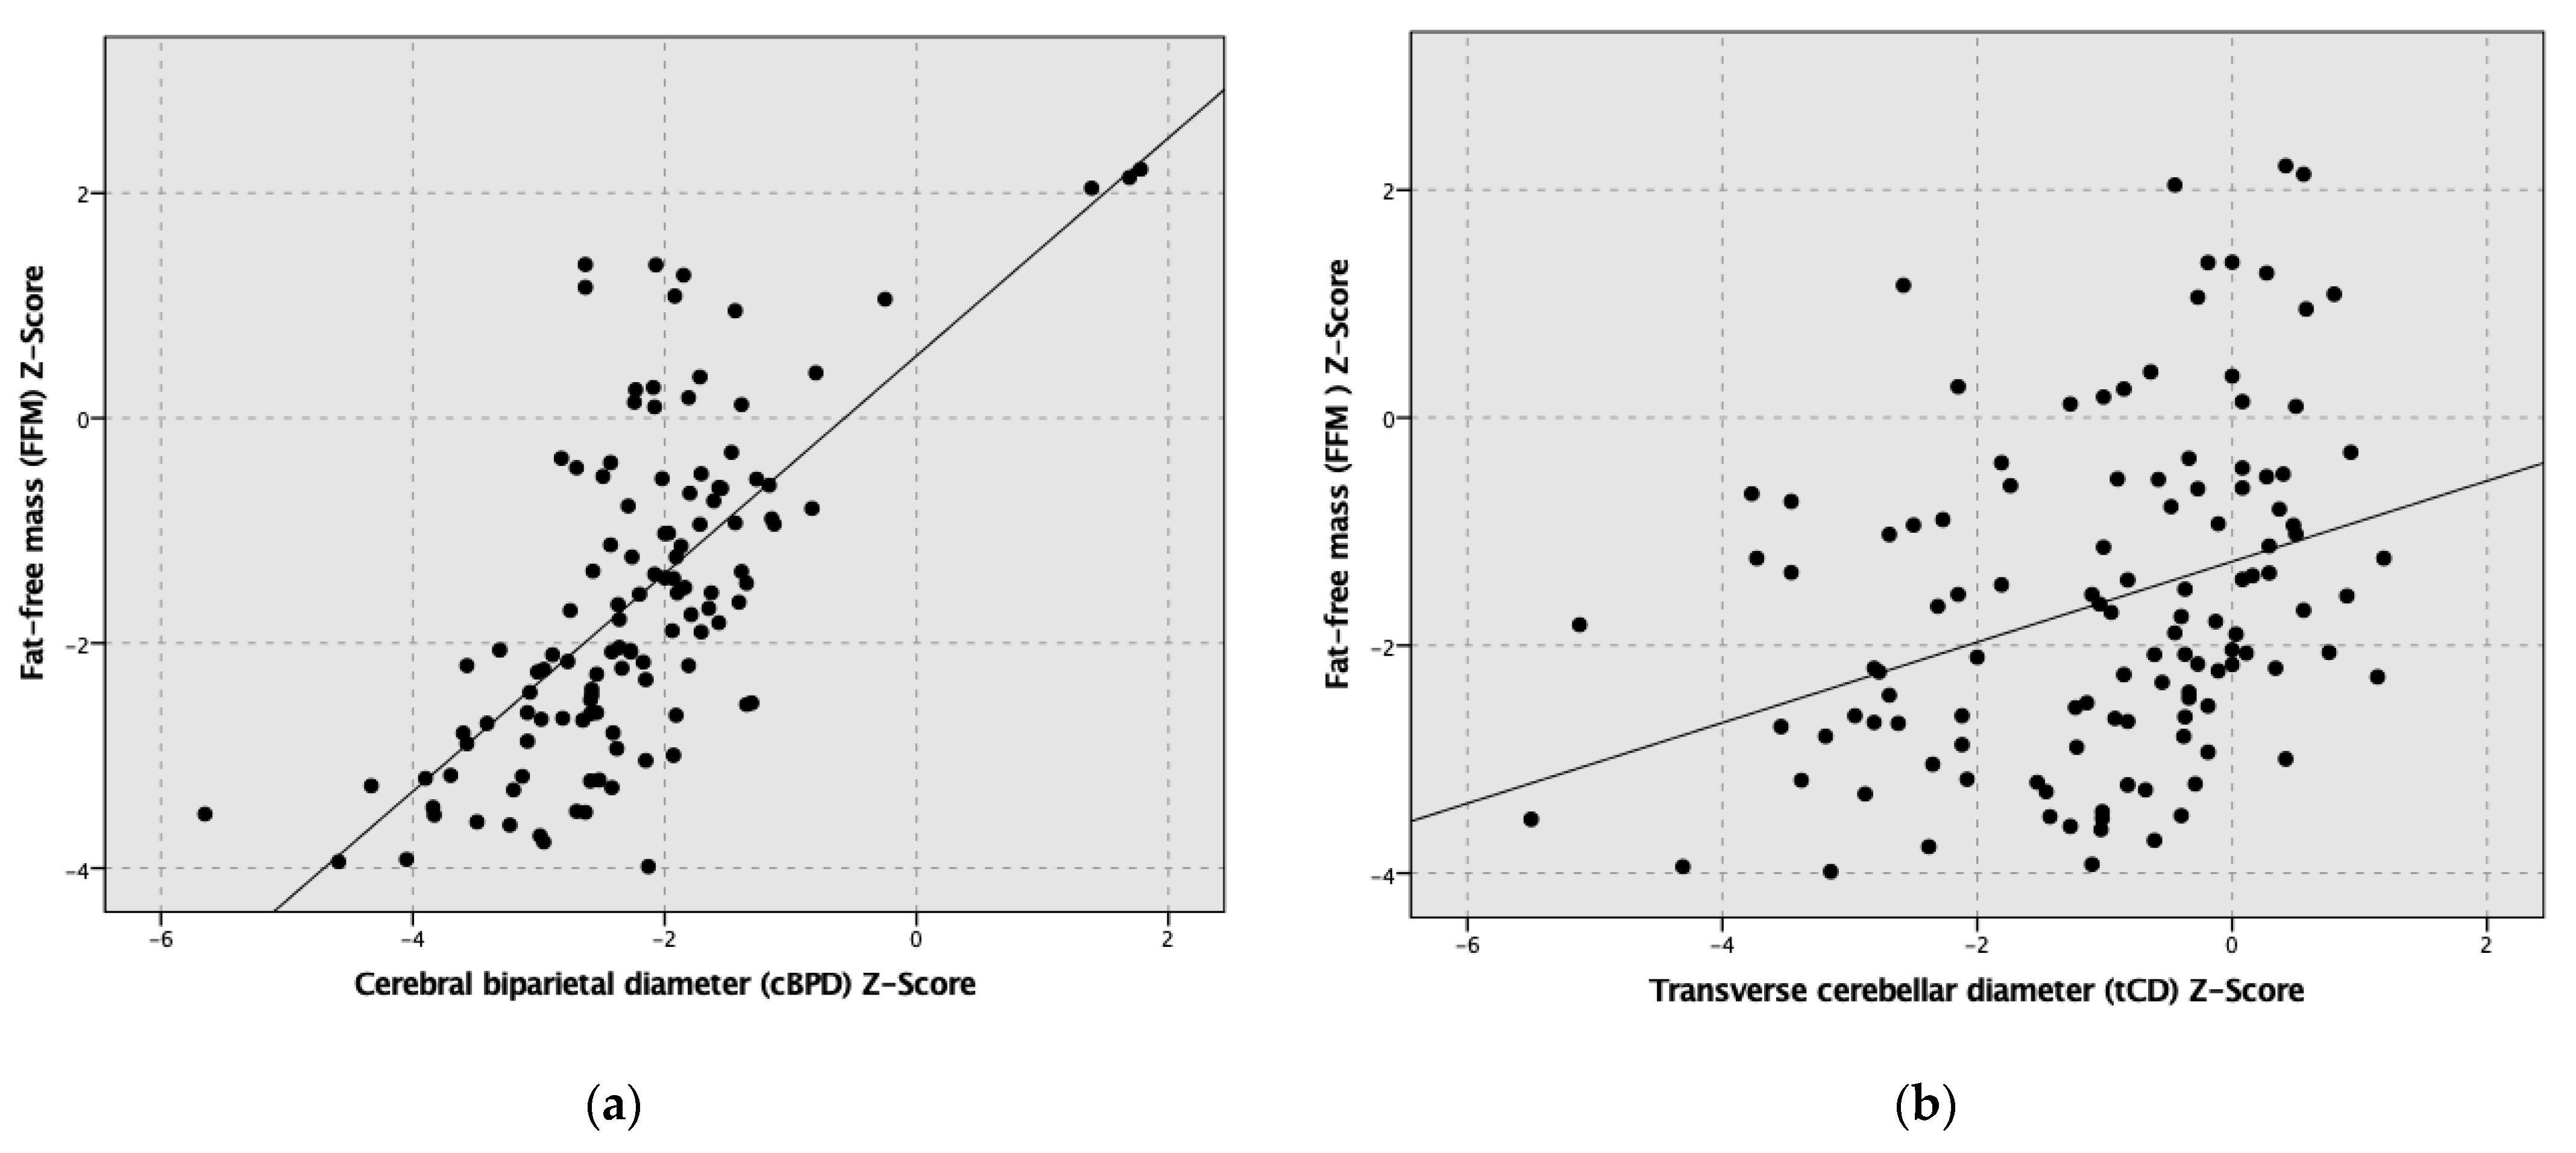

3. Results

4. Discussion